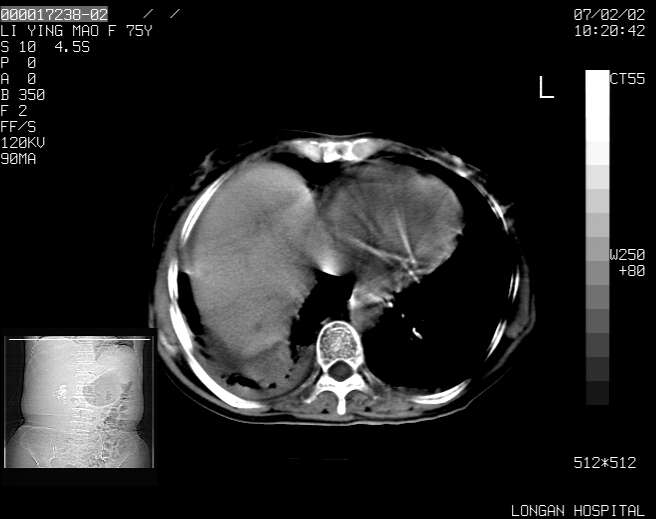

以下是引用dyqct在2007-2-10 8:53:00的发言:[br]考虑:1、肝脏多发囊肿[br] 2、左肾囊肿,右肾多发结石并积水。[br] 3、右胸少量积液。[br] 4、右肾周包裹性积液或淋巴管瘤(有见缝就钻的征象、薄隔、小结节状钙化)?[br] 5、腰椎动脉瘤样骨囊肿?[br] [br] [br]